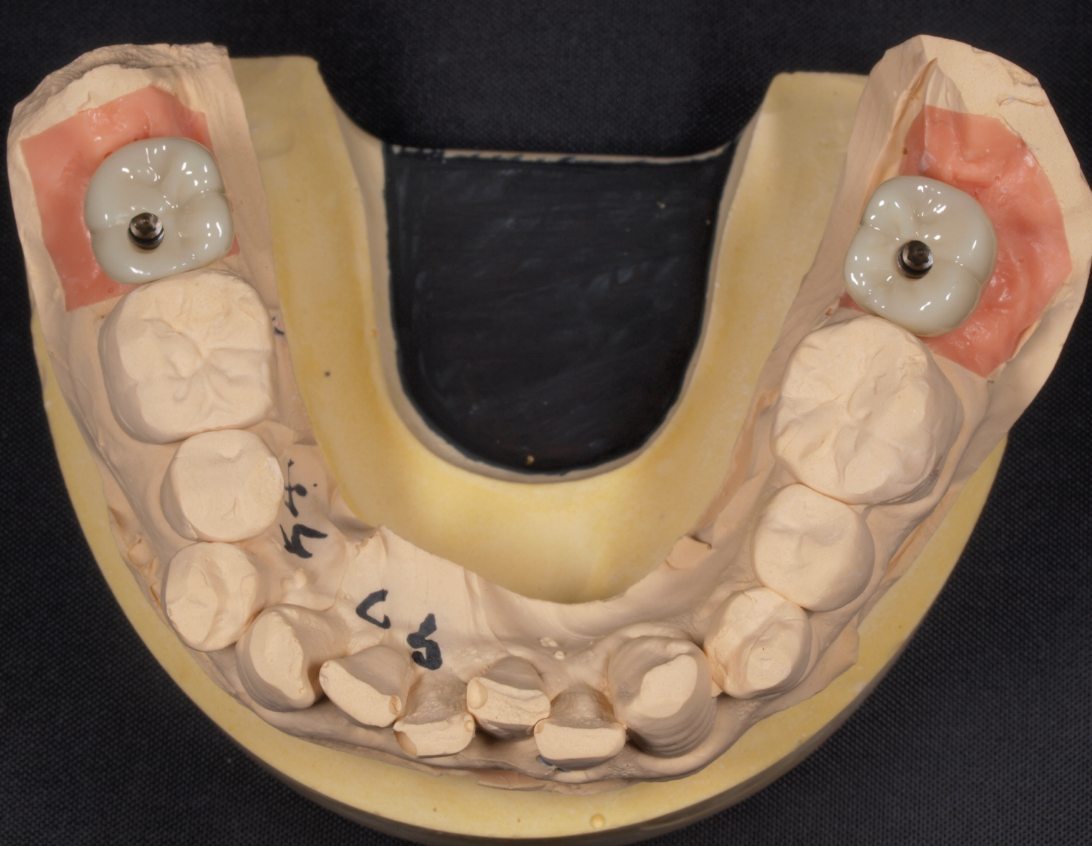

上顎をAll-on-4™(オールオン4) で治療した症例(50代男性)

BEFORE

AFTER

患者様の主訴

今までその都度歯科治療を繰り返していたが、結局どれもあまり長く持たず、すぐに他も悪くなってぼろぼろになってしまうのでこの際時間とお金はかかっても良いので、しっかりと長くもつインプラント歯科治療をして欲しい。

診断結果

上顎は虫歯と歯周病で残念ながら全て抜歯の適応でした。患者様はまだ50代というご自身の年齢と、今後のQOL(クオリティオブライフ)を検討した結果、現在の残ってる数本の歯を抜歯して即時手術で固定の人工歯が入ってその日からお食事可能なインプラント治療のオールオン4治療を選択されました。また下顎はご自身の歯を全て残す治療が選択可能でした。

治療内容

手術当日に上顎の予後不良な歯を全て抜歯して、同時に4本のノーベルバイオケア社製、ノーベルスピーディーRPを4本埋入しました。後方のインプラントは、上顎洞を避け、傾斜埋入としました。後にマルチユニットアバットメントを装着後に印象(型取り)を行い、同日にプロビジョナルレストレーション(仮歯)を装着し、即時荷重を達成しました。プロビジョナルレストレーションはインプラント専門んの技工士さんに立ち会いにより、審美的・機能的に満足したものとなりました。患者様は1日でお口の中に歯が入り、ご帰宅されました。もちろん次の日からご勤務などの社会復帰は可能です。

約10ヶ月ほどプロビジョナルレストレーション(仮の上部構造)の調整を行いながら使用していただき噛み合わせなどの使用感や顔貌との調和、滑舌などの問題がなく良好にお過ごしいただけたので、ここから最終補綴物(ボーンアンカードブリッジ)作製に入りました。最終補綴物(ボーンアンカードブリッジ)の為の印象採得(型取り)を行い、数回の試適や噛み合わせの決定などを経てジルコニアセラミック製の最終補綴物(ボーンアンカードブリッジ)が患者様に装着されました。下顎はジルコニアセラミックを印象採得して装着しました。

補綴物

治療後経過

インプラント治療終了後から約4年経過していますがオールオン4インプラントは全く問題なく経過良好です。

| 治療期間 | 約1年6ヶ月 |

|---|---|

| 治療にかかった費用 | All-on-4™インプラント埋入手術1,994,400円(静脈内鎮静麻酔代含む)+上顎ジルコニアセラミック上部構造2,640,000円+下顎ジルコニアセラミッククラウン143,000×8本分+上下WAXUP模型代55,000円 |

| リスク副作用 | インプラントは入れたら終わりではなく、きちんとメンテナンスしないと歯周病になることもあるので、定期的にクリーニングや噛み合わせの調整が必要です。 |